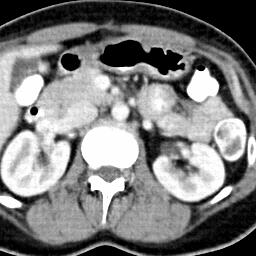

Due to the constraints of the imaging device and high cost in operation time, computer tomography (CT) scans are usually acquired with low intra-slice resolution. Improving the intra-slice resolution is beneficial to the disease diagnosis for both human experts and computer-aided systems. To this end, this paper builds a novel medical slice synthesis to increase the between-slice resolution. Considering that the ground-truth intermediate medical slices are always absent in clinical practice, we introduce the incremental cross-view mutual distillation strategy to accomplish this task in the self-supervised learning manner. Specifically, we model this problem from three different views: slice-wise interpolation from axial view and pixel-wise interpolation from coronal and sagittal views. Under this circumstance, the models learned from different views can distill valuable knowledge to guide the learning processes of each other. We can repeat this process to make the models synthesize intermediate slice data with increasing inter-slice resolution. To demonstrate the effectiveness of the proposed approach, we conduct comprehensive experiments on a large-scale CT dataset. Quantitative and qualitative comparison results show that our method outperforms state-of-the-art algorithms by clear margins.